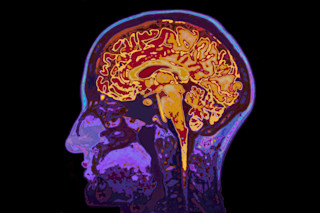

Of all frightening ways that the SARS-COV-2 virus affects the body, one of the more insidious is the effect of COVID-19 on the brain.

It is now clear that many patients suffering from COVID-19 exhibit neurological symptoms, from loss of smell, to delirium, to an increased risk of stroke. There are also longer-lasting consequences for the brain, including myalgic encephalomyelitis /chronic fatigue syndrome and Guillain-Barre syndrome.

These effects may be caused by direct viral infection of brain tissue. But growing evidence suggests additional indirect actions triggered via the virus’s infection of epithelial cells and the cardiovascular system, or through the immune system and inflammation, contribute to lasting neurological changes after COVID-19.